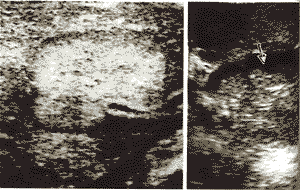

44例肝癌共有肿瘤结节76个,术前超声与术中超声的诊断率分别为84%(6 4/76)与97%(74/76),后者明显高于前者(P<0.05),其中肿瘤结节直径>2cm≤5cm计52个 ,术前超声与术中超声的诊断率分别为98%(51/52)与100%(52/52),二者无统计学差异(P >0.05),而对肿瘤直径≤2cm结节的诊断率,术中超声为92%(22/24),明显高于术前超声 的54%(13/24)(P<0.01)(表1),本组中术中超声检出的最小肿瘤直径仅为4mm。此外表 中 也显示本组44例肝癌已有17例(39%)表现门静脉或/和肝静脉转移,而术中超声诊断率达94%( 16/17),明显高于术前超声对血管内瘤栓的诊断率54%(9/17)(P<0.01),尤其位于肝 小静脉内的栓子术前超声更不易发现,本组术中超声还发现2例肝内胆管内瘤栓(图1)。

, 百拇医药 图1 术中超声:左图可见肝癌部分压迫门静脉分支,右图可见扩张胆管后壁瘤栓(箭头所示)